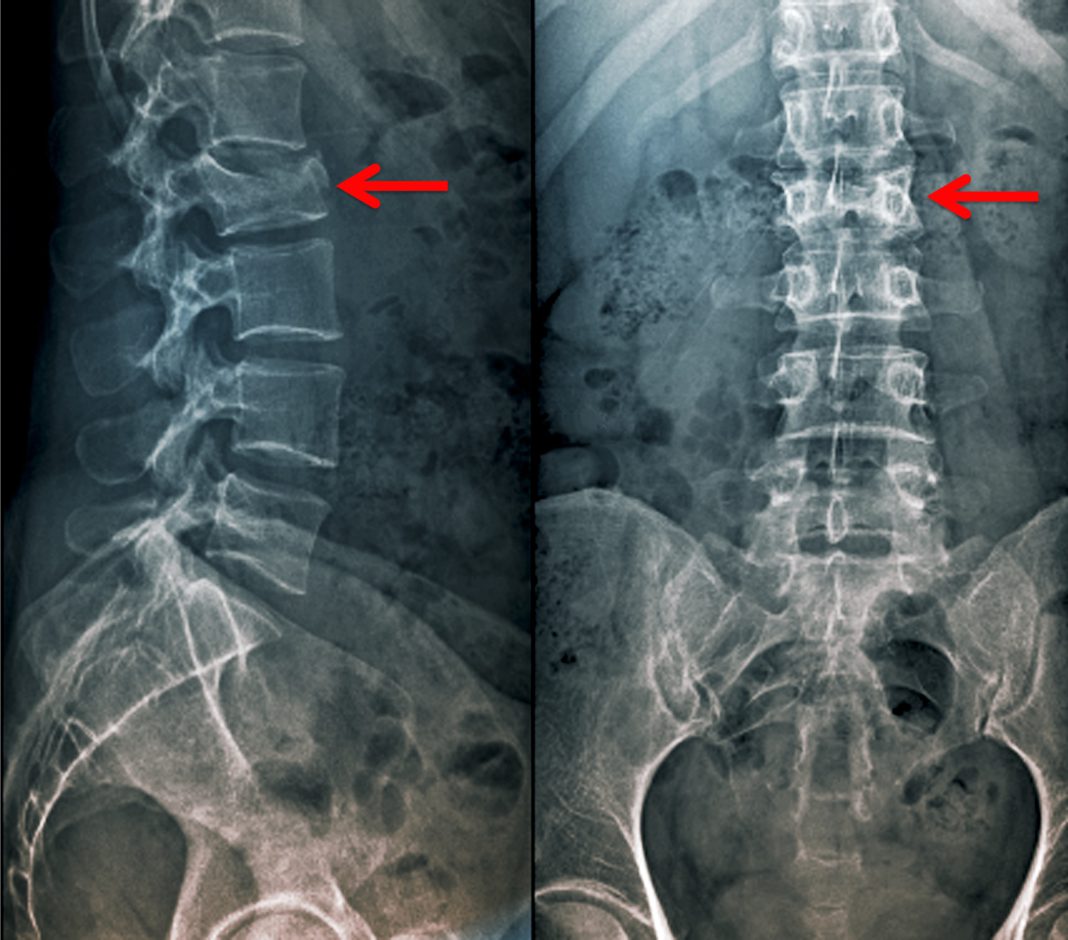

From www.researchgate.net

(A), preoperative lumbar spine Xray shows wedge shape deformity of L4... Download Scientific What Is A Wedge Deformity Wedge fractures cause the front of a vertebra to compress, leading to spinal deformity. Indications would include severe fracture with neurologic injury, severe angulation, failure to heal with initial bracing, increased angulation. The fracture forms on the front of the vertebra. The broken bone collapses and takes on a wedge shape. Vertebral wedge fractures are the most common osteoporosis fracture. What Is A Wedge Deformity.

(A), preoperative lumbar spine Xray shows wedge shape deformity of L4... Download Scientific What Is A Wedge Deformity The name wedge fracture, refers to the wedge. Indications would include severe fracture with neurologic injury, severe angulation, failure to heal with initial bracing, increased angulation. There are three types of compression fractures: The broken bone collapses and takes on a wedge shape. Wedge fracture — this fracture usually occurs in the front of the vertebra, collapsing the bone in.. What Is A Wedge Deformity.